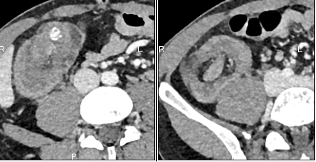

Le CT scanner abdominal montre une invagination iléo-cæcale sur environ 8 cm, sans signe de souffrance intestinale (absence de pneumatose pariétale ou de liquide libre). La valve iléo-cæcale présente un épaississement circonférentiel discrètement irrégulier, accompagné d’une calcification de 17 mm (stercolithe). L’appendice est non distendu, et aucune adénomégalie suspecte n’est observée.

Coupe transverse